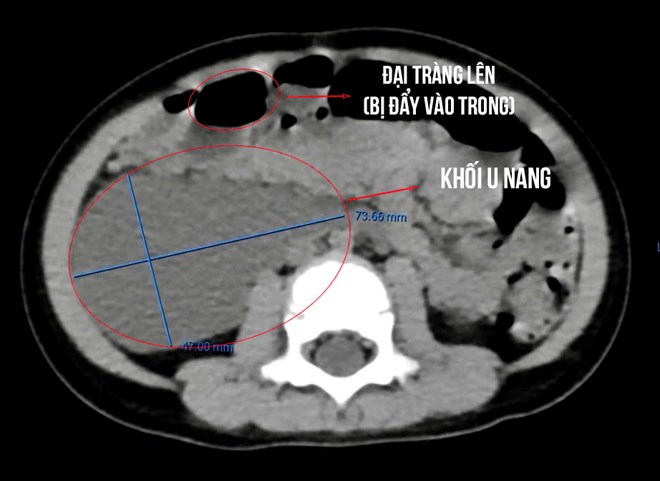

Bé 26 tháng tuổi mang u nang lớn hiếm gặp. Ảnh: Bệnh viện Đa khoa TTH Quảng Bình

Kết quả siêu âm ổ bụng cho thấy từ vùng hạ sườn phải xuống hố chậu phải có một cấu trúc dạng nang kích thước lớn. Hình ảnh chụp CT xác định khối u nang chiếm gần nửa vùng bụng phải, đẩy toàn bộ quai ruột sang bên trái.

Trong quá trình mổ, ê-kíp ghi nhận khối u nang lớn nằm sau phúc mạc, khiến toàn bộ đại tràng phải bị đẩy lệch vào giữa ổ bụng và nằm sát các cấu trúc quan trọng như thận, niệu quản và bó mạch chậu phải. Các bác sĩ tiến hành bóc tách cẩn trọng, giải phóng các cấu trúc liên quan và cắt bỏ hoàn toàn khối u.